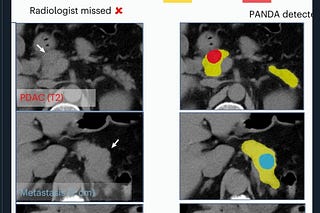

Advanced Endoscopic Imaging: The Quest for Virtual Histology

The Promise of Seeing What Only the Microscope Can See